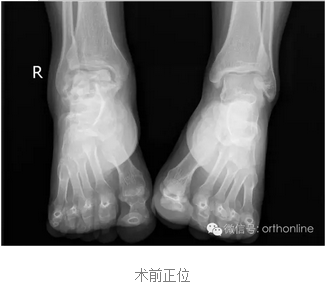

世界上首例3D打印的具有生物学功能的个性化假体治疗距骨塌陷性坏死在重庆获得成功

创伤引起的距骨塌陷性坏死一直是医学界面临的难题,治疗手段非常有限,目前只能采用以牺牲踝关节生物学功能的胫-距-跟植骨融合来缓解病人的痛苦,严重影响患者生活质量。

针对上述问题,由第三军医大学西南医院唐康来教授牵头,中国科学院重庆绿色智能技术研究院、物质结构研究所、金属研究所、化学研究所、理化技术研究所等十个单位协作攻关,分别从3D打印设备与专用材料、个体性产品开发与临床应用方面进行研究,研制了世界上首个3D打印的具有生物学功能的个性化距骨假体,于2016年7月4日在重庆第三军医大学西南医院成功应用于创伤引起的距骨塌陷性坏死病例。

塌陷性距骨坏死一直是踝关节假体置换的绝对禁忌症,该假体打破了常规,为塌陷性距骨坏死提供了非常好的选择。